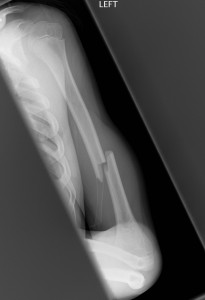

Above: Spiral fracture of shaft of humerus

Shaft Fractures

- Shaft fractures of the humerus are less common than proximal or distal (supracondylar) fractures.

- Transverse fractures generally occur from a direct blow and spiral fractures from a twisting mechanism.

- Consider non-accidental injury in younger children with spiral fractures. Discuss with senior ED doctor and Child Protection Unit if concern for NAI.